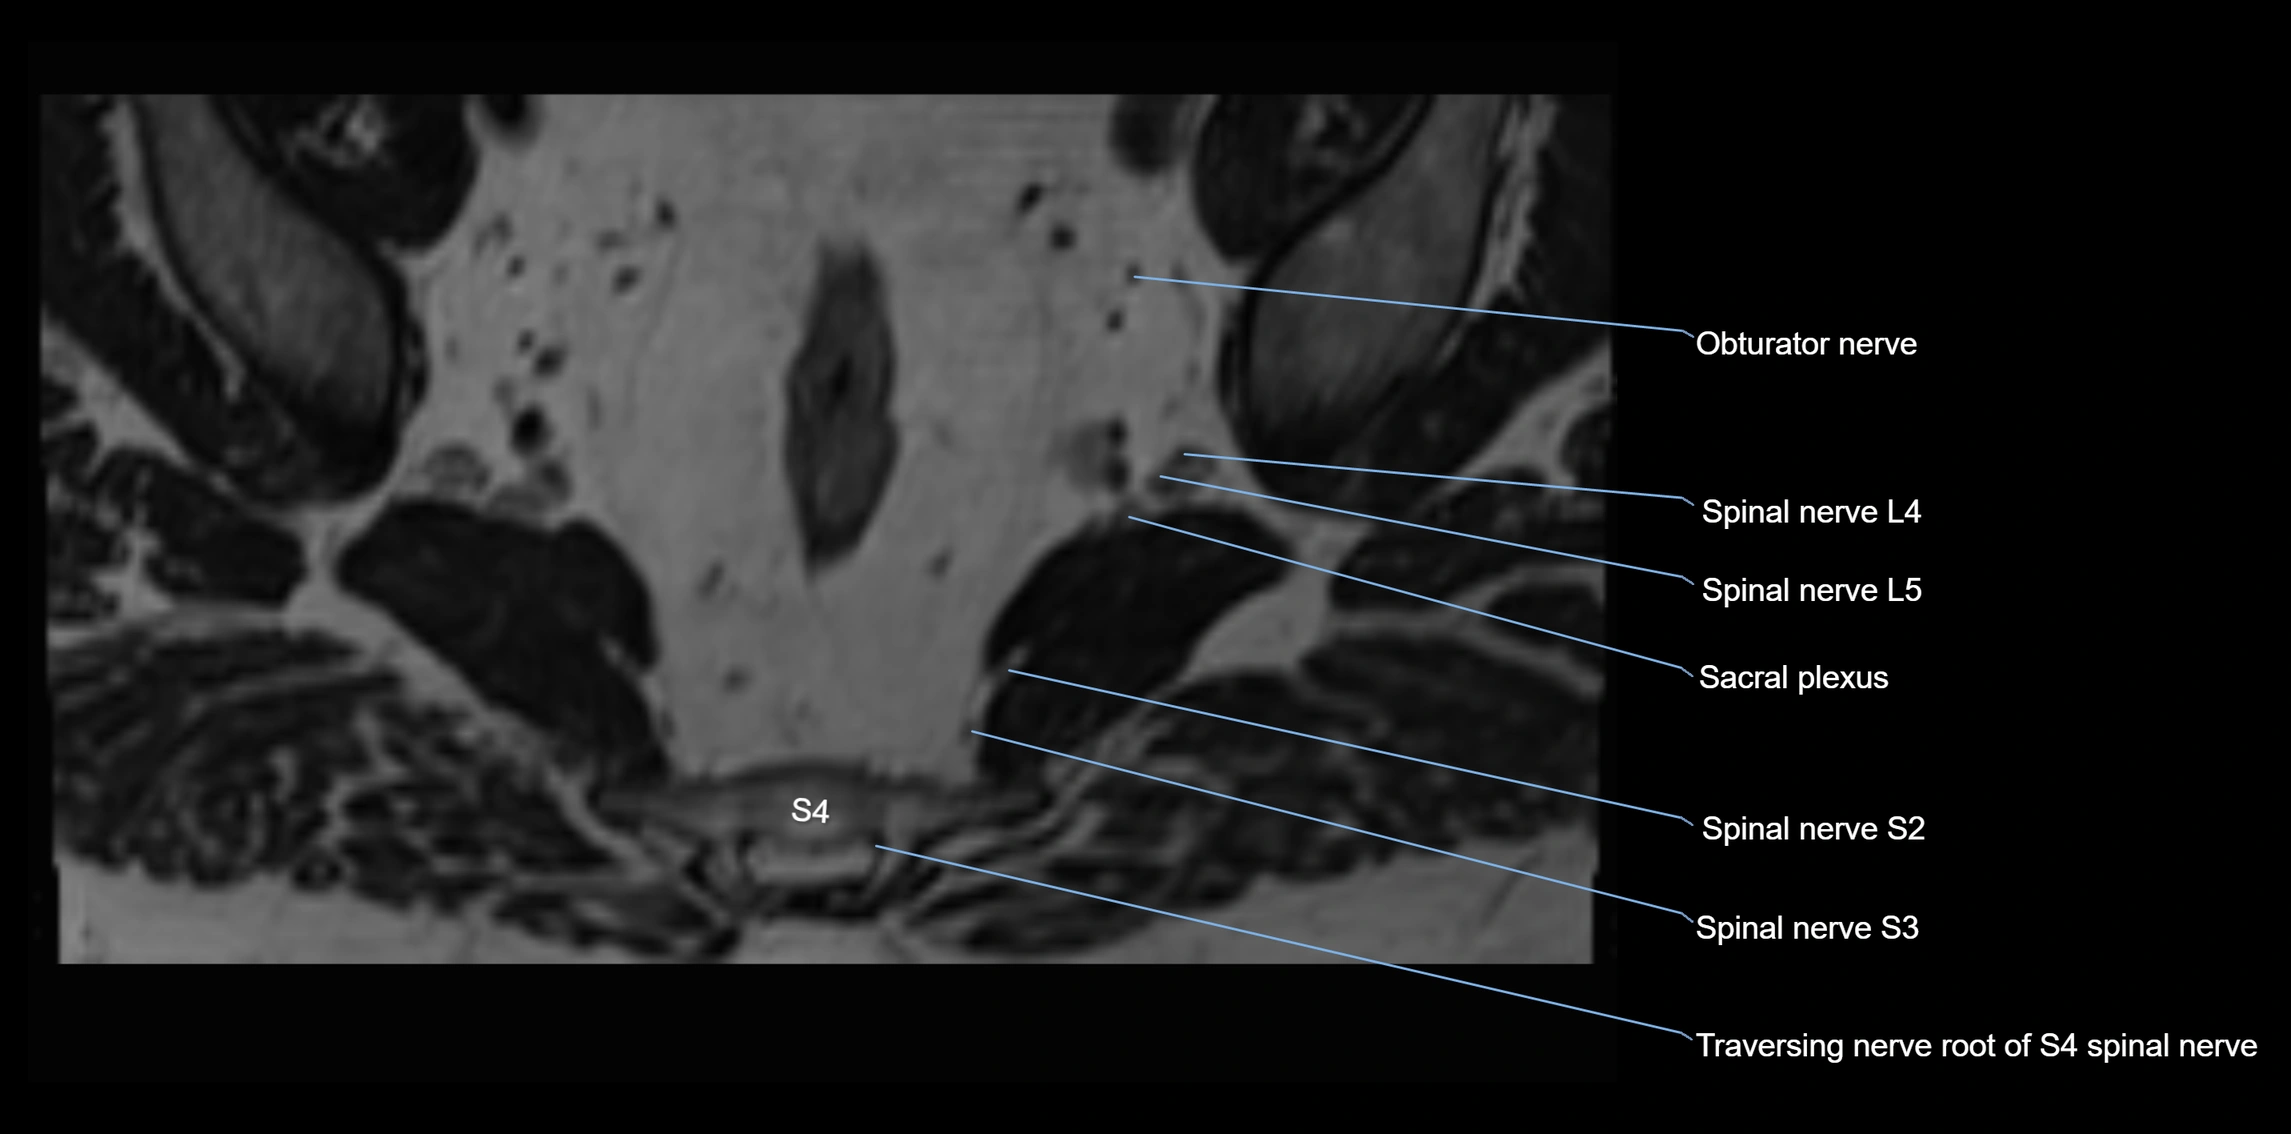

MRI Appearance

T1-weighted images:

• Nerve appears as a very thin low-to-intermediate signal intensity structure

• Surrounded by bright fat, aiding visualization

T2-weighted images:

• Nerve shows intermediate to mildly hyperintense signal compared to muscle

• Pathological involvement appears brighter

STIR (Short Tau Inversion Recovery):

• Normal nerve appears dark

• Inflamed or entrapped nerve appears bright hyperintense

T1 Fat-Sat Post-Contrast:

• Normal nerve enhances minimally

• Pathologic nerve (neuritis, entrapment, tumor infiltration) shows focal or diffuse enhancement

3D T2 SPACE / CISS:

• Nerve appears intermediate to mildly hyperintense compared to muscle

• Surrounded by bright fat or CSF, improving visualization

• Best sequence for mapping small pelvic nerves such as the anococcygeal

MRI image

image